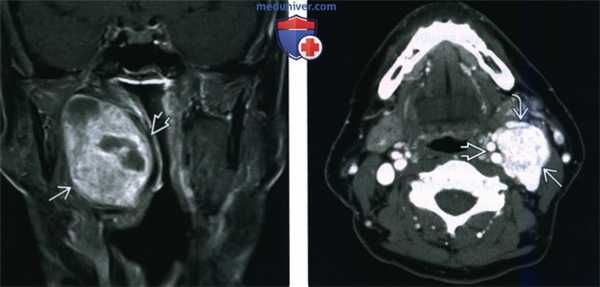

(Слева) МРТ Т1ВИ FS с КУ, аксиальная проекция. В задних отделах подподъязычного сонного пространства расположено образование округлой формы. Шваннома симпатического ствола смещает и сонную артерию, и внутреннюю яремную вену кпереди. Одновременное смещение обоих сосудов сонного пространства весьма характерно для шванномы симпатического ствола.

(Справа) МРТ Т1ВИ FS c КУ, коронарная проекция. Шваннома симпатического ствола, расположенная в сонном пространстве. Опухоль неравномерно накапливает контрастное вещество. Участки кистозного перерождения в крупных шванномах встречаются достаточно часто.